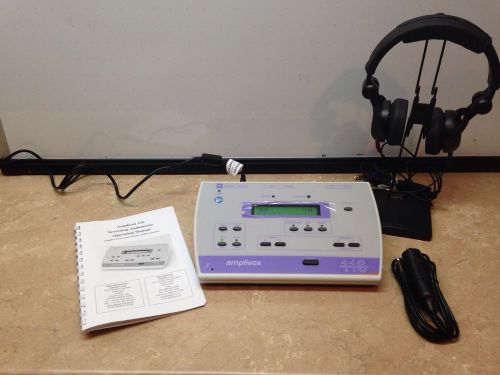

Amplivox 116 Screening Audiometer, **NEW!!** 5-Year Warranty